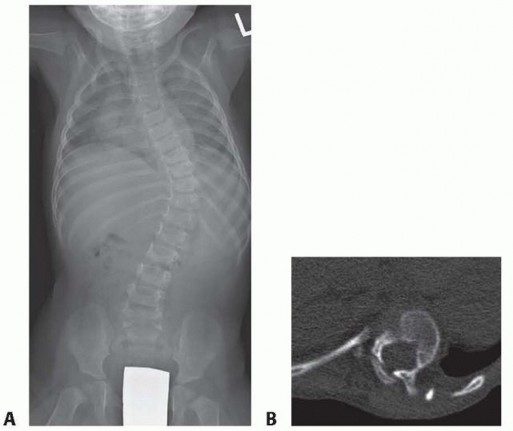

Hemivertebra Excision DEFINITION A hemivertebra is a congenital anomaly of the spine that forms during the 8t…

Growing Rod Instrumentation for Early-Onset Scoliosis DEFINITION Early-onset scoliosis (EOS) is defined by th…